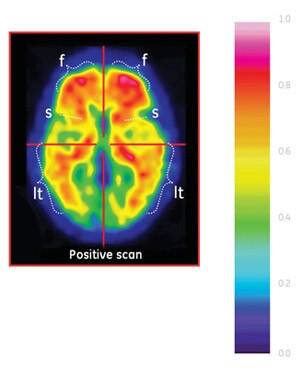

For the visualization of β-amyloid neuritic plaque density in patients being evaluated for cognitive disorders, including Alzheimer's disease...Introducing the first-and-only amyloid imaging agent with FDA approval for color image interpretation.

Vizamyl is indicated for positron-emission tomography (PET) imaging of the brain to estimate β-amyloid neuritic plaque density in adult patients with cognitive impairment who are being evaluated for Alzheimer's disease and other causes of cognitive decline.1

• A positive Vizamyl scan indicates moderate to frequent amyloid neuritic plaques

• Neuropathological examination has shown that this amount of amyloid neuritic plaque is present in patients with Alzheimer's disease, but it may also be present in patients with other types of neurologic conditions as well as in older people with normal cognition

PRODUCT INDICATIONS AND USAGE: Vizamyl™ (Flutemetamol F 18 Injection) is indicated for positron-emission tomography (PET) imaging of the brain to estimate β-amyloid neuritic plaque density in adult patients with cognitive impairment who are being evaluated for Alzheimer's disease (AD) and other causes of cognitive decline. A negative scan indicates sparse to no neuritic plaques, inconsistent with a diagnosis of AD at the time of image acquisition. A negative scan result reduces the likelihood that a patient's cognitive impairment is due to AD. A positive scan indicates moderate to frequent amyloid neuritic plaques. This amount of amyloid neuritic plaque has been shown to be present in patients with AD but may also be present in patients with other neurologic conditions as well as in older people with normal cognition. Vizamyl is an adjunct to other diagnostic evaluations. Limitations: A positive scan does not establish a diagnosis of AD or other cognitive disorder. The safety and effectiveness of Vizamyl have not been established for predicting the development of dementia or other neurologic conditions or for monitoring responses to therapies.